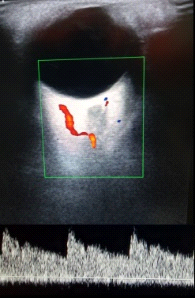

Ophthalmic artery: flows similar to those of the internal carotid (low resistance), high systolic peak, dicrotic incisura and low diastolic flow (Figure 2).

Figure 2 Spectrum of the ophthalmic artery.

Spectrum of the ophthalmic artery: The retinal vasculature is supplied by the ophthalmic artery (OA). The retina is one of the most metabolically active tissues in the body and consumes high levels of oxygen and nutrients. It therefore has a well-organized vascular system that is adapted to meet its metabolic requirements to ensure visual function.

Central retinal artery and vein: one arterial and one venous flow, anterograde and retrograde at 2 mm anterior to the optic nerve shadow (Figure 3).

Figure 3 Central retinal artery and vein.

Spectrum of the central retinal artery and vein: In this order of ideas, the velocimetric evaluation of the spectrum allows discerning the vascular structure in question, which when it takes values between 25 and 45 cm/sec points to the presence of the ophthalmic artery that can vary, but if the velocity is similar or less than 10 cm/sec it is more likely to be over the central retinal artery that has lower velocities.

Retinal circulation is influenced to a lesser extent by blood pressure (BP) and postural changes due to its self-regulating capacity; however, it can be affected by increases in intraocular pressure (IOP). For this reason it is important not to exert pressure on the eyeball when applying the ultrasound probe as this would raise the IOP and alter the blood flow results.15-17